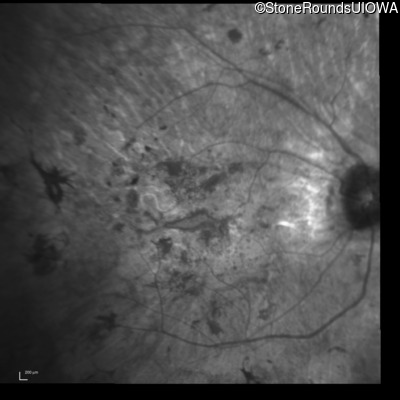

Optical Coherence Tomography - Right - Hand Motion

Exemplar / OCT Stack

OCT Stack

Infrared Fundus Photograph - Right - Hand Motion

Exemplar